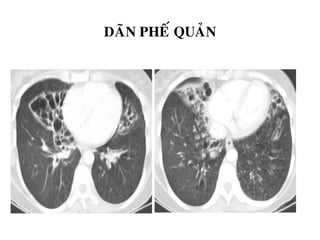

DAÕN PHEÁ QUAÛN ( BRONCHIECTASIS)

Daõn pheá quaûn vôùi daáu hieäu voøng nhaãn (signet ring sign): pheá quaûn lôùn hôn

ñoäng maïch ñi keøm (bình thöôøng khi tæ soá pheá quaûn/maïch maùu < 1.2)

Daõn pheá quaûn vôùi daáu hieäu ñöôøng ray ( ‘tram line’ sign): do daõn pheá

quaûn daïng truï khi pheá quaûn song song vôùi maët caét .

DAÕN PHEÁ QUAÛN